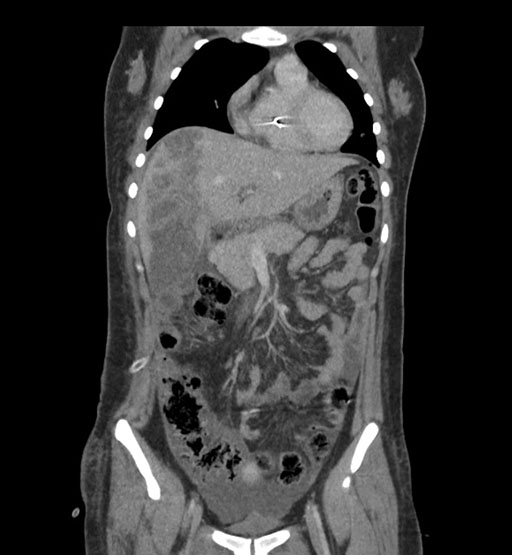

Coronal Arterial

Coronal Venous